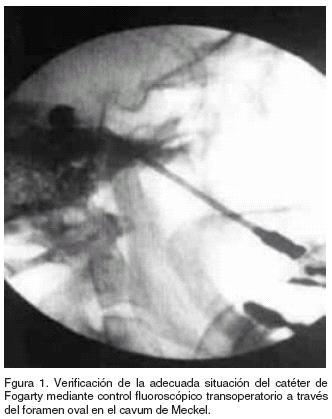

Anestesia general ligera, intubación orotraqueal, decúbito dorsal, punción percútanea, con aguja del número 14 de acuerdo a la técnica de Hartel descrita por Nugeet,9 canulación del agujero oval, corroboración de colocación adecuada mediante intensificador de imágenes, en proyección AP y lateral, introducción de sonda de Fogarty número tres, introducida de 15 a 20 mm después de la punta de la aguja, insuflación del balón a 0.7cm, hasta obtener una imagen en forma de pera durante seis minutos, corroborando la adecuada colocación con el intensificador de imágenes (Figura 1).